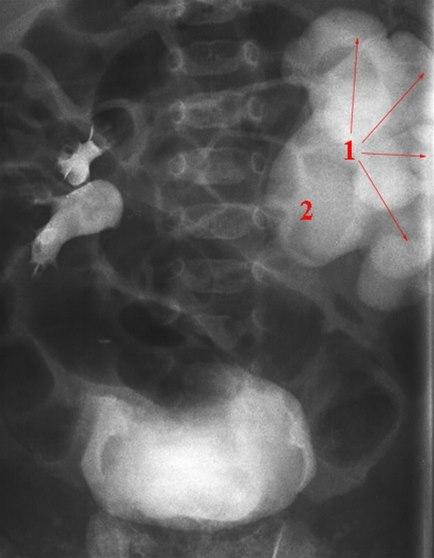

Kraftig utvidelse av calyces (1) og ekstrarenalt nyrebekken (2) på pasientens venstre side

Ureter er ikke utvidet.